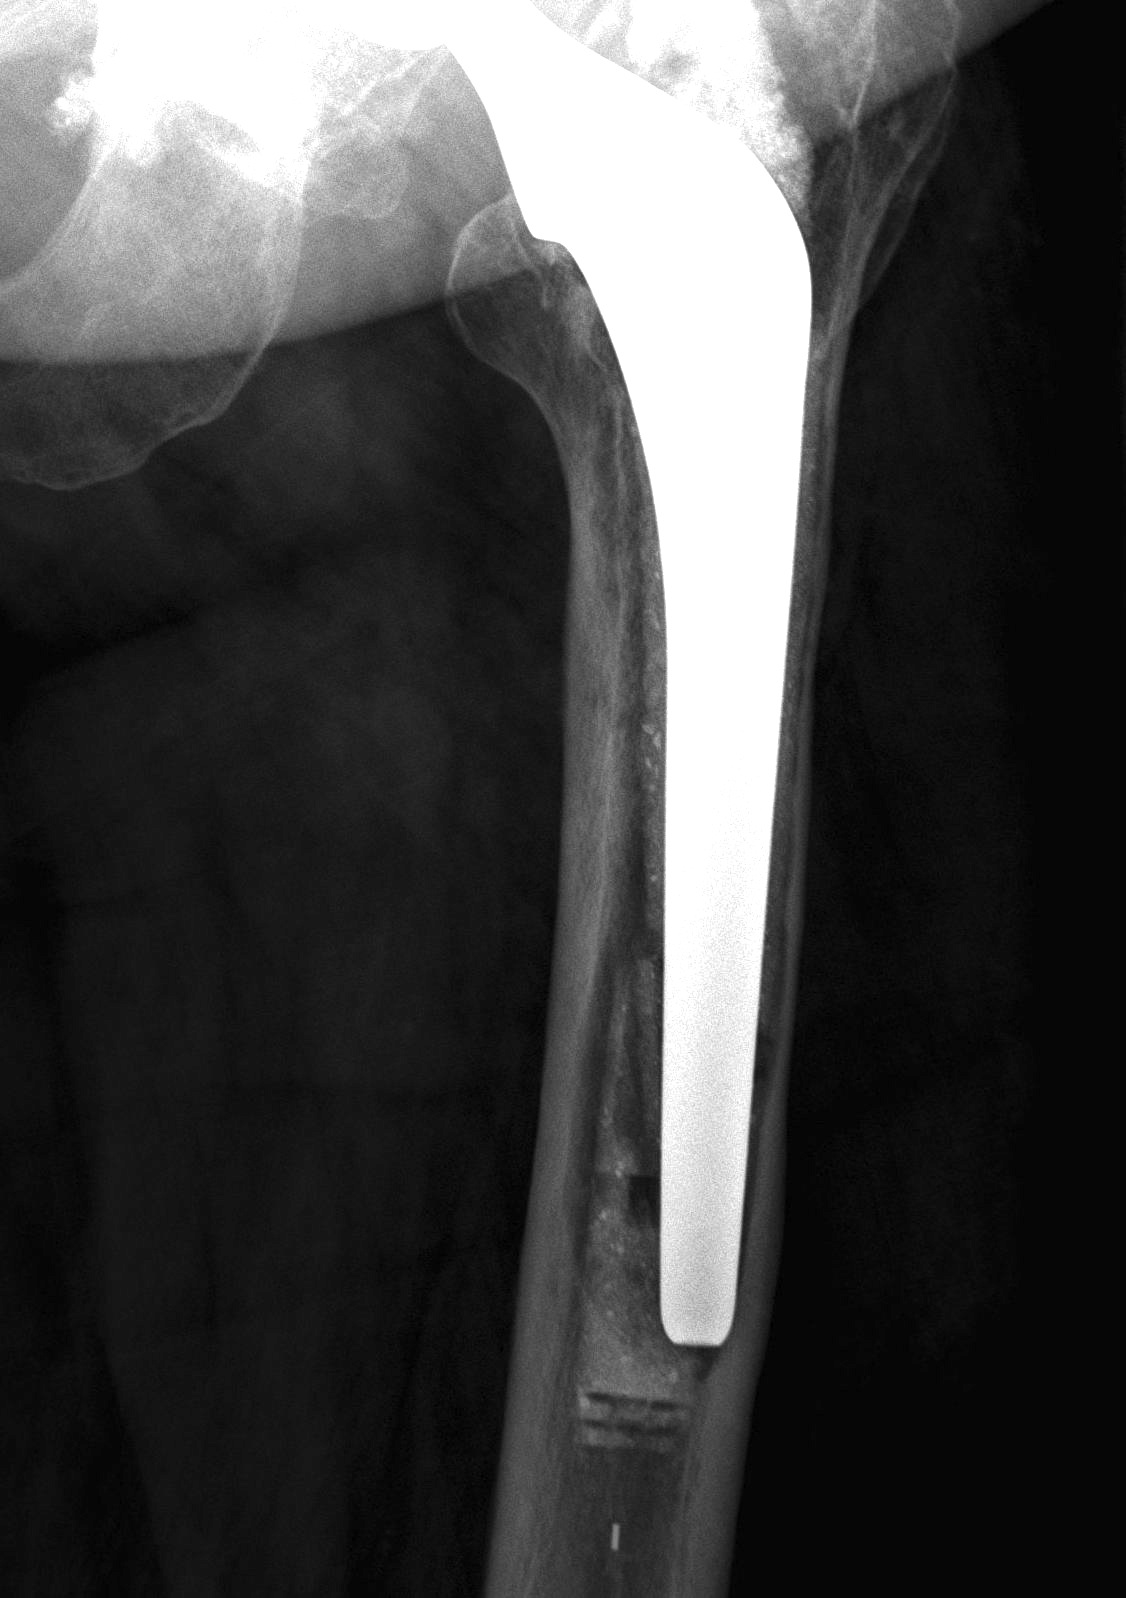

Barrack's femoral component cementation quality grading system

| Grade | Definition |

|---|---|

| A | Complete filling of the medullary canal, without radiolucent lines between the cement and the bone (white-out) |

| B | Radiolucent line covering up to 50% of the cement-bone interface |

| C | Radiolucent line covering between 50% and 99% of the cement-bone interface or incomplete cement mantle |

| D | Complete radiolucent line (100%) at the cement-bone interface and/or absence of cement distally to the end of the stem |

Grade A Grade B Grade C Grade D